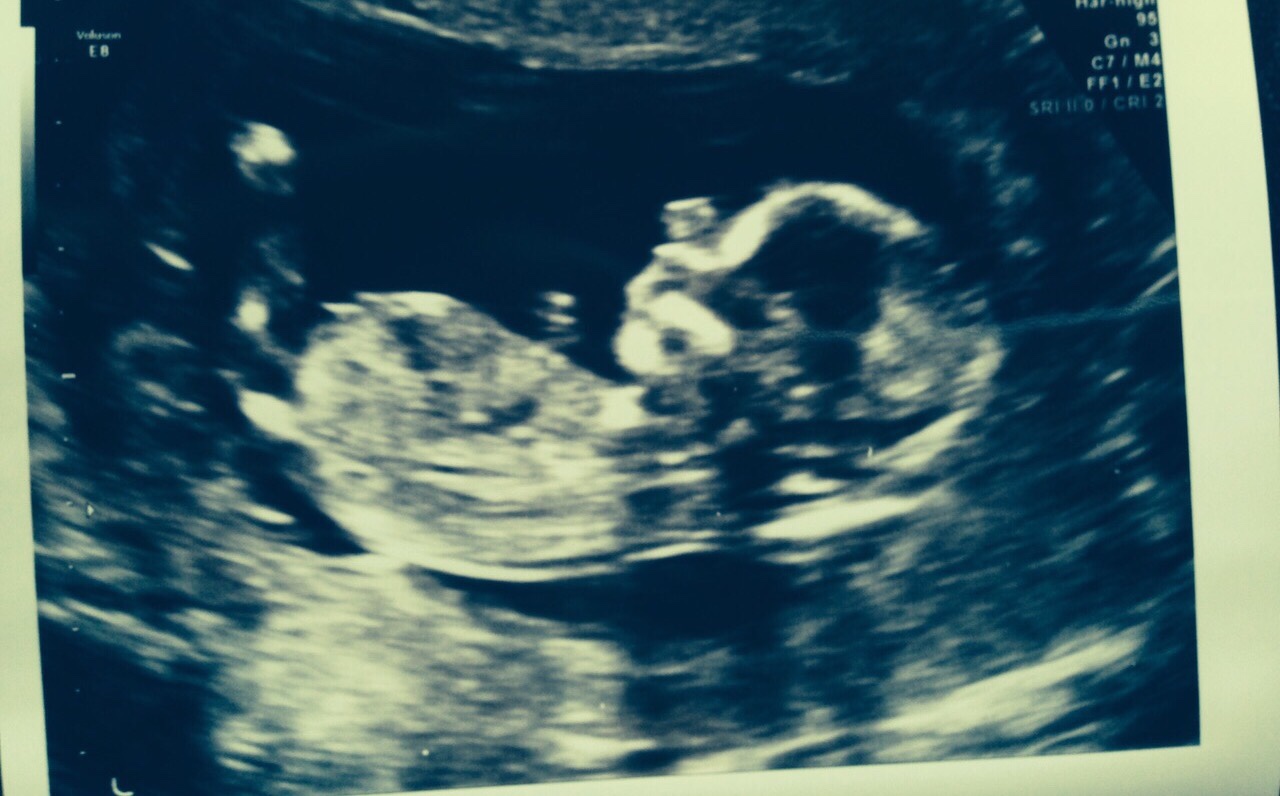

Here is a 12 week scan from a friend. I said I'd ask you girls for your opinions. Boy or girl? TIA

Never seen a nub like that before (and I have 3 boys!) but yeah if that bright spot that looks like a golf club is the nub then its gotta be a boy!

Skull looks boy too

IF that's the nub I think I'm seeing, I'm going to lean girl. FX!

Leaning boy

Just to confirm my friend had a boy.